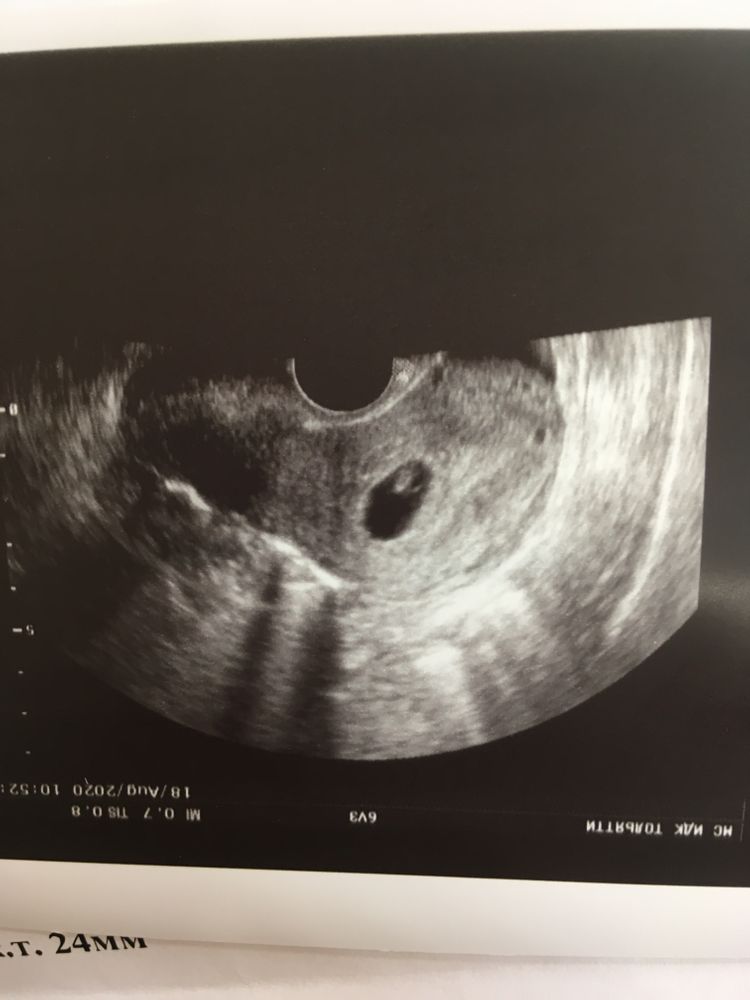

Приветик! Вчера сильно разболелся живот, скорее всего кишечник. Бок левый внизу болел и отдавало в поясницу. Решила записаться на узи, посмотреть малышочка и ещё почки проверить на всякий случай. Все вроде и неплохо, только снова тонус ставят сильный, на...

Всем привет! Напоминаю, что лежу в больнице из-за плохого роста хгч и угрозой зб. Сегодня ходила на узи. Врач долго что-то смотрел и молчал. Я чуть с ума не сошла. Спрашиваю его «что-то не так?». Он говорит «почему?». Я спрашиваю появился ли эмбрион. Он ...

Девочки, пишу снова в это сообщество, никак не могу перейти в беременность) Тут прям душа) Сегодня было пожалуй самое переживательное узи, ждала вердикт, так как неделю назад не увидели сб! Да и вообще знаете, что у меня то хгч плохо рос, то живот болел (все в дневнике, если что). Так вот, все у нас хорошо! Врач сказал, что развивается по сроку и сб хорошее (но чсс не считали). Дала мне посмотреть на экране, как стучит сердечко 💓 моего малыша!